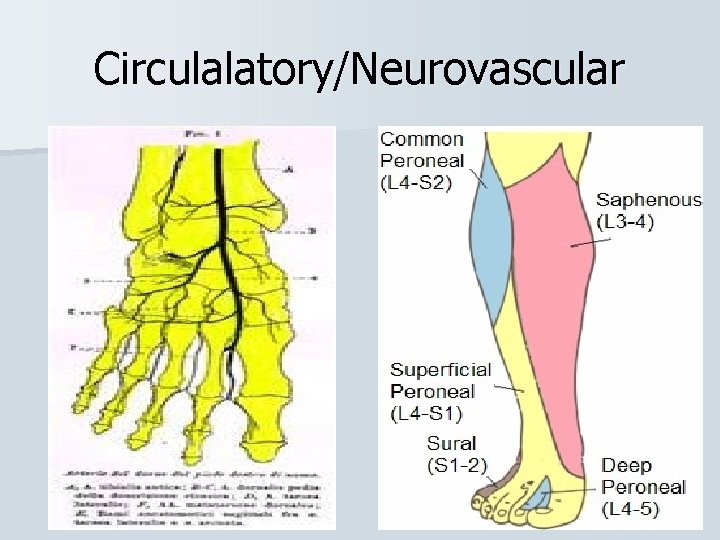

Circulalatory/Neurovascular